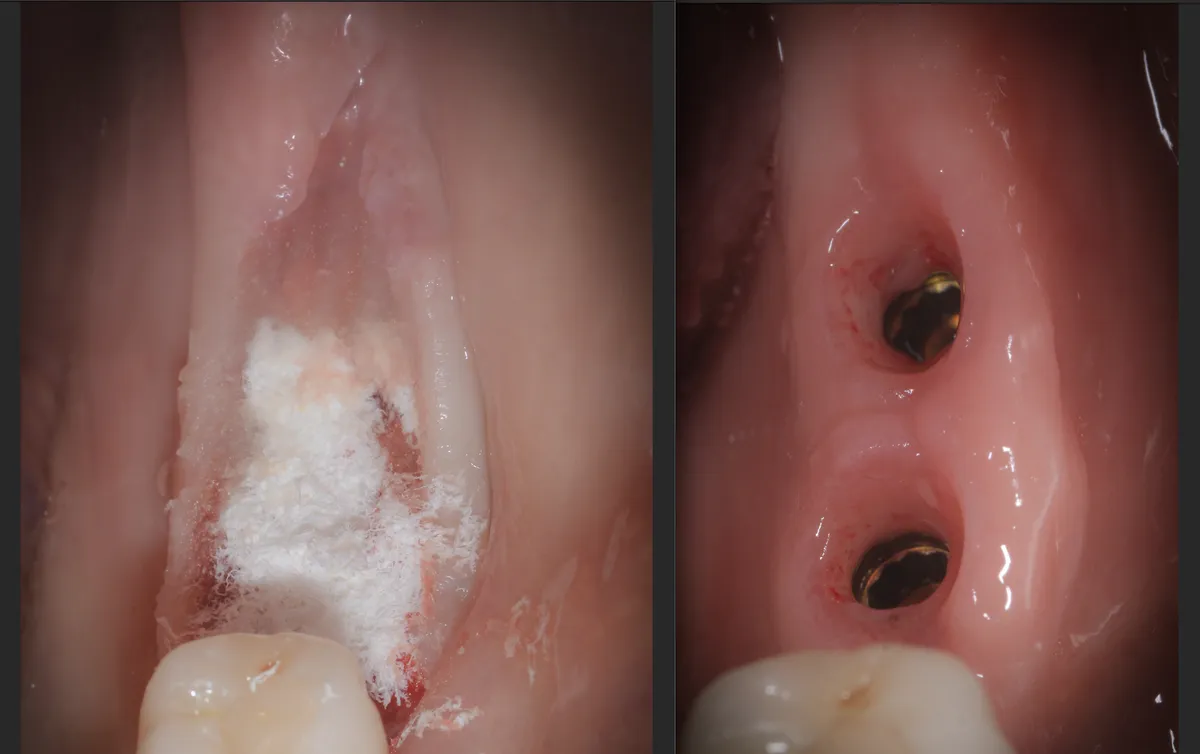

Caso clinico: espansione crestale ERE con impianto immediato e rigenerazione simultanea. Da ponte fallito a impianto in un'unica seduta.

Bonebenders: espansione osteo-mucosa naturale per impianti. 100% osso e mucosa cheratinizzata senza biomateriali. Caso clinico e risultati straordinari.

Paper 2024 su Gingival Open-Wound Technique: "innovazione" o riscoperta? Dr. Bruschi documenta guarigione per seconda intenzione nell'implantologia da...

Scopri come il tuo corpo guarisce naturalmente senza suture. La guarigione per seconda intenzione: il processo che rigenera osso e tessuti per impianti ...